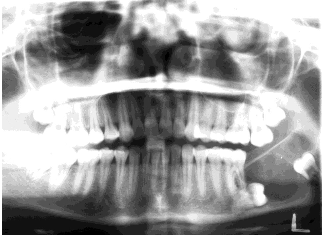

What thought process should you follow when you see a radiolucency on a radiograph?

What are the different types of multilocular radiolucencies seen in radiographs of the head and neck?